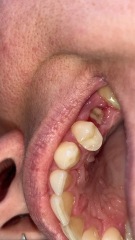

Had lower right molar yanked out in a tug of war battle 4 days ago. Up until today there was a very obvious grey jelly goo level with the rest of the gum. Woke this morning and either the top layer has fallen out, or sunken further in. Just looks more hollow than it has the last few days. Is that normal at this stage or am I on my way to a dry socket? No pain (well, except a mild throbbing which has steadily improved since the extraction).

Also, when is my mouth going to stop tasting like a bag of sour arseholes? I don't think it's infected, there's no swelling or pus/leakage or anything, it just tastes awful! Regularly salt water rinsing.